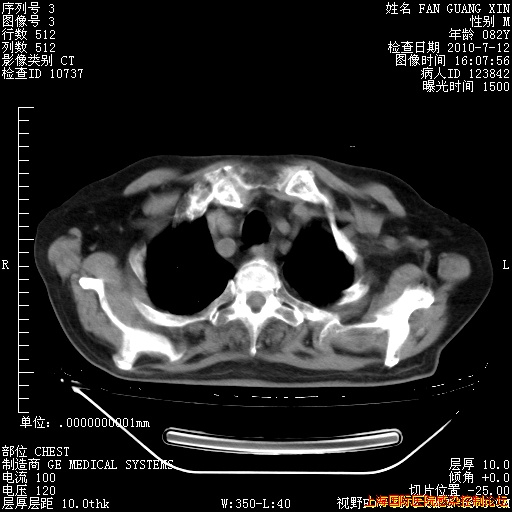

6月12日纵膈窗

回复